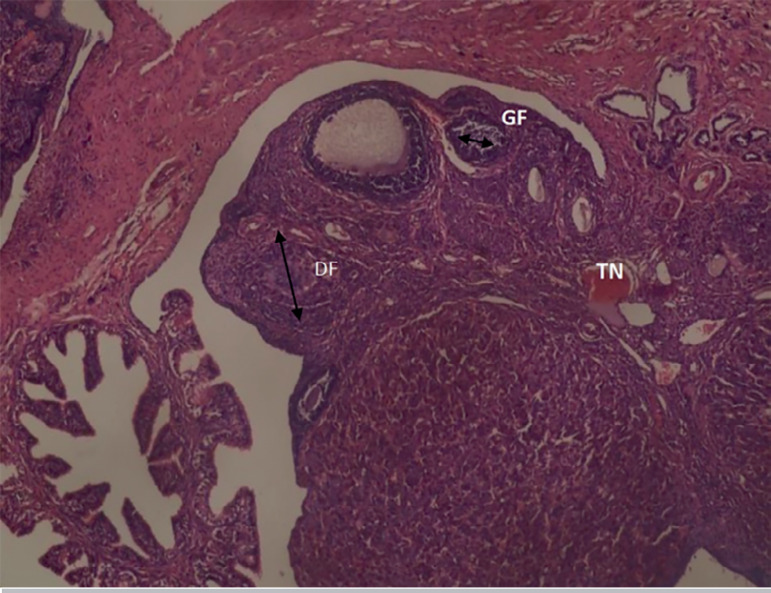

Results: The body weight of the rats showed a dose-dependent reduction (p<0.05), compared with the controls. Xylopia aethiopica seeds significantly (p<0.05) reversed the detrimental effects of Cadmium on LH and FSH. The histological analysis of the ovary showed significant improvement upon treatment with Xylopia aethiopica extract in a dose-dependent manner.